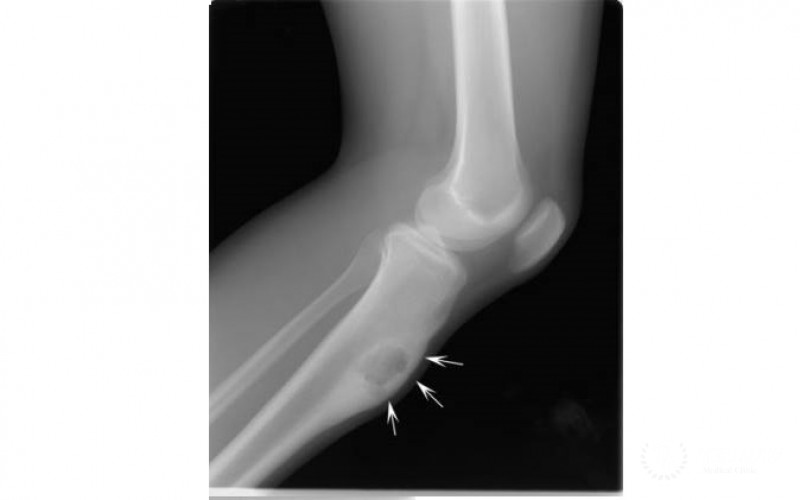

- Рентгеновское обследование. Оценка уровня повреждения костной ткани;